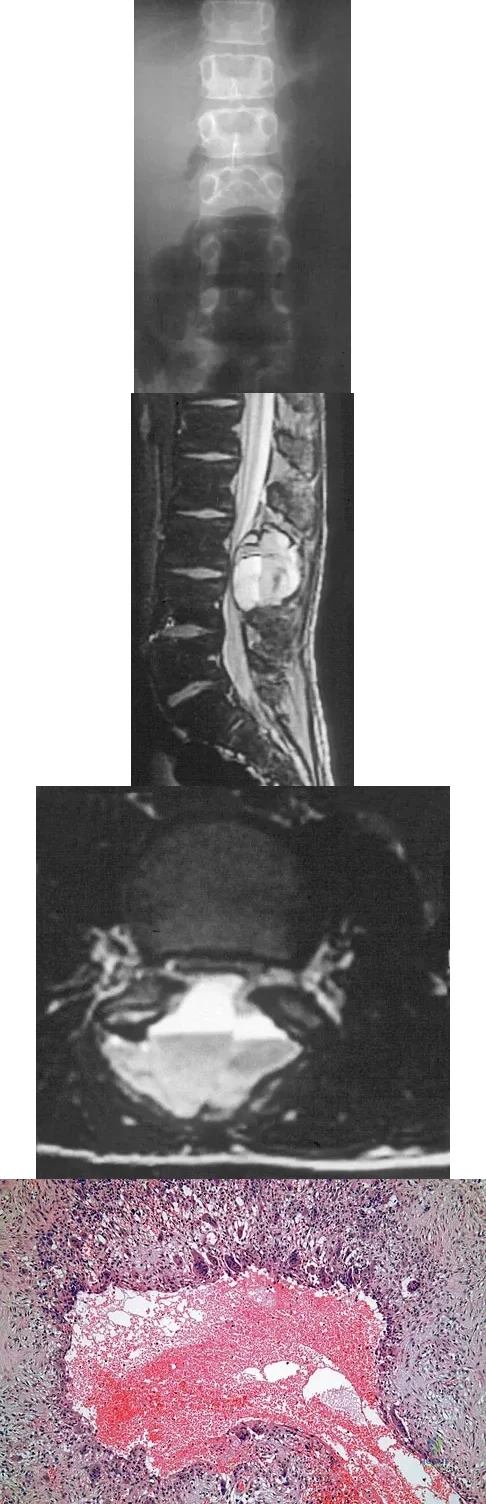

Question 62

An 8-year-old boy is diagnosed with acute onset cauda equina syndrome. A radiograph, MRI scans, and a biopsy specimen are shown in Figures 57a through 57d. What is the most appropriate treatment?

Explanation